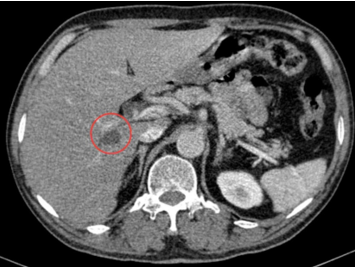

- Chụp cắt lớp vi tính tầng trên ổ bụng (24/09/2024): Gan kích thước bình thường, bờ đều. Nhu mô hai bên rải rác có vài nang , nang lớn đường kính 16mm. Hạ phân thùy VII, VIII có 2 nốt ngấm thuốc mạnh đồng nhất thì động mạch và tĩnh mạch đường kính 6mm và 8mm. Tiền liệt tuyến kích thước 56x39x41mm tương đương 45gram.

Hình 3. Hình ảnh nốt gan phải (ô màu đỏ) ngấm thuốc mạnh đồng nhất thì động mạch và tĩnh mạch.